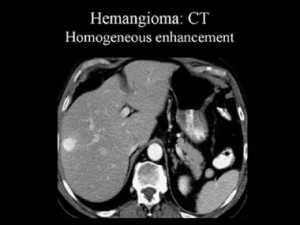

Так, гемангиома печени на КТ без контраста выглядит как гиподенсный участок, природу которого установить затруднительно. В артериальную фазу контрастирования наблюдается значительное увеличение плотностных характеристик гемангиомы (из-за накопления контрастированной крови в сосудистых лакунах), но затем ее плотность снижается и постепенно приходит к прежним значениям, что позволяет отличить гемангиому печени от рака, так как злокачественные новообразования, например, рак кишечника с метастазами в печень при КТ с контрастированием проявляется иначе: для метастазов наиболее характерно усиление плотности в виде «кольца» («ободка»), которое отображает активную (васкуляризованную) часть опухоли.

Гемангиома печени или рак? КТ брюшной полости с контрастным усилением: типичное накопление контраста в виде лакун помогает дифференцировать гемангиому от рака и установить правильный диагноз: кавернозная гемангиома.

5) Гемангиома правой доли печени, либо левой доли. Гемангиома печени на КТ выглядит как типичный гиподенсный очаг, при контрастировании в артериальную фазу резко усиливается, в результате чего становятся видимыми сосудистые лакуны, а затем медленно теряет контраст. Атипичные гемангиомы на КТ имеют несколько другие характеристики, и отличить их от злокачественного поражения помогает взгляд опытного рентгенолога, имеющего опыт в диагностике заболеваний брюшной полости.